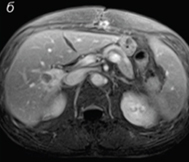

Resonancia magnética después de 30 días de tratamiento